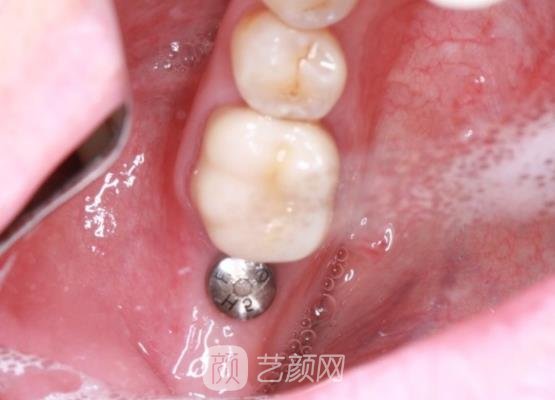

种植牙手术案例介绍

来到这个科室以后,这里的口腔医生为我做了全方面的检查,并且还问了我个人的一些想法,还给我看了一下口腔里边的具体情况,在都准备好了之后,接下来就要开始进行手术了,其实做手术之前我并没有太大的把握,怕一旦做不好的话,可能会给口腔带来一些伤害。

不过在接下来的几个小时里,我还是很配合医生的,按照医生交给我的每一步细心的操作,所以整个手术下来还是比较轻松,也没有用了多长时间,在完成手术之后,我按照医生的交代,做好术后的每一步护理工作,所以现在我的牙齿恢复的很好,我很满意。